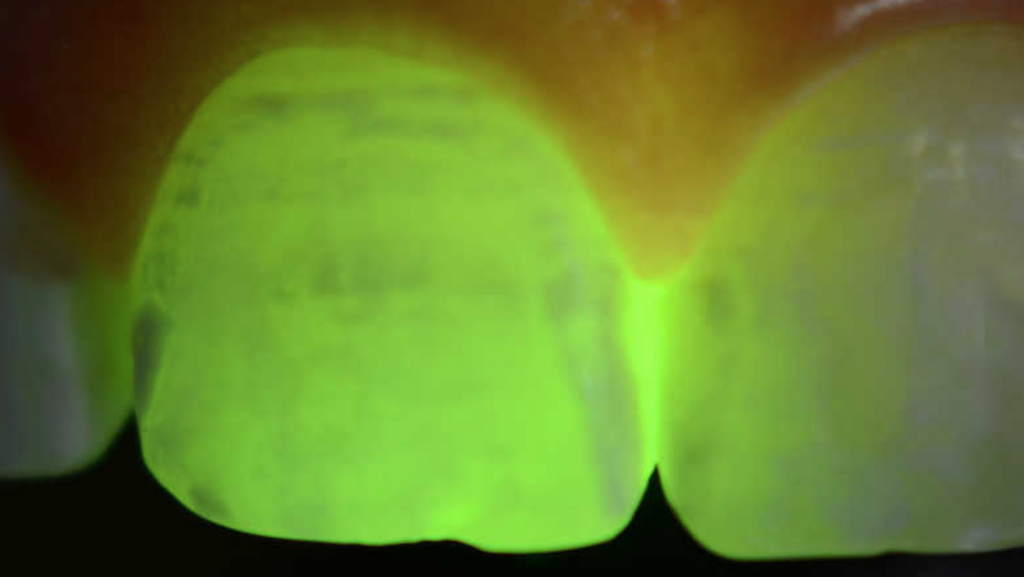

Diagnostico: La evaluación inicial del dentista para determinar si el diente es adecuado para el tratamiento ICON generalmente toma unos minutos. Durante esta etapa, el dentista examina las manchas blancas y decide si son candidatas para la infiltración con resina. Lo normal es que se utilice un metodo de transiluminación o de detección de caries (DIAGNODENT) para valorar la profundidad de dichas manchas.